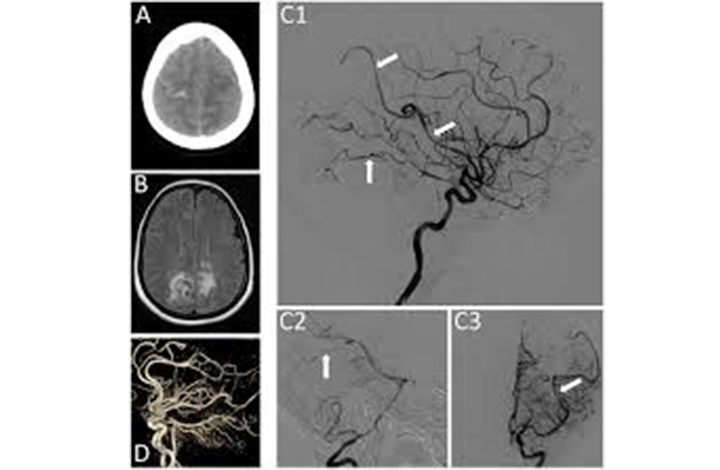

Cath Lab

A catheterization laboratory, commonly referred to as a cath lab, is an examination room in a hospital or clinic with diagnostic imaging equipment used to visualize the arteries of the heart and the chambers of the heart and treat any stenosis or abnormality found.

DSA

Digital subtraction angiography is used to produce images of the blood vessels without interfering shadows from overlapping tissues.